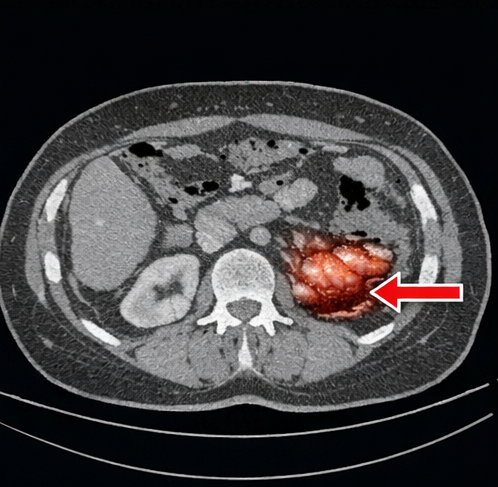

Contrast-enhanced computed tomography (CT) abdomen revealed segmental thickening of the terminal ileum with mucosal enhancement but no perforation.